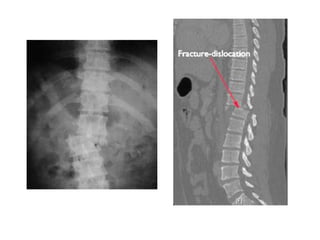

Fracture-Dislocation

• Failure of all columns

(compression, tension,

rotation, or shear).

• anterior hinge is disrupted.

• Dislocation.

• Severe neurological deficit.

Fracture-Dislocation • Failure ofall columns (compression, tension, rotation, or shear). • anterior hinge is disrupted. • Dislocation. • Severe neurological deficit.